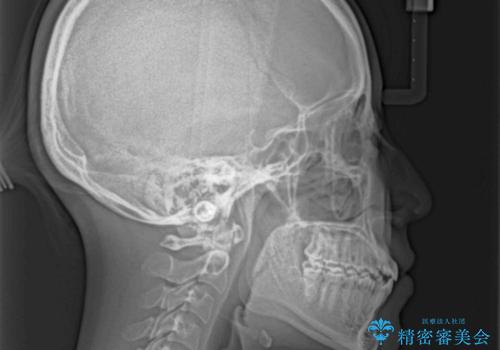

受け口と開咬を急速拡大装置とワイヤー装置で改善

- 前歯の開咬と、受け口による咬み合わせの悪さを気にして来院された患者様です。

上顎歯列が狭窄していたため、急速拡大装置により上顎骨を側方に拡大し、その後ワイヤー装置にて矯正治療を行うこととしました。

舌の突出癖が開咬の原因であったので、改善のための舌トレーニングを行っていただきました。

舌トレーニングは後戻りにも大きく影響するため、とても重要なトレーニングです。